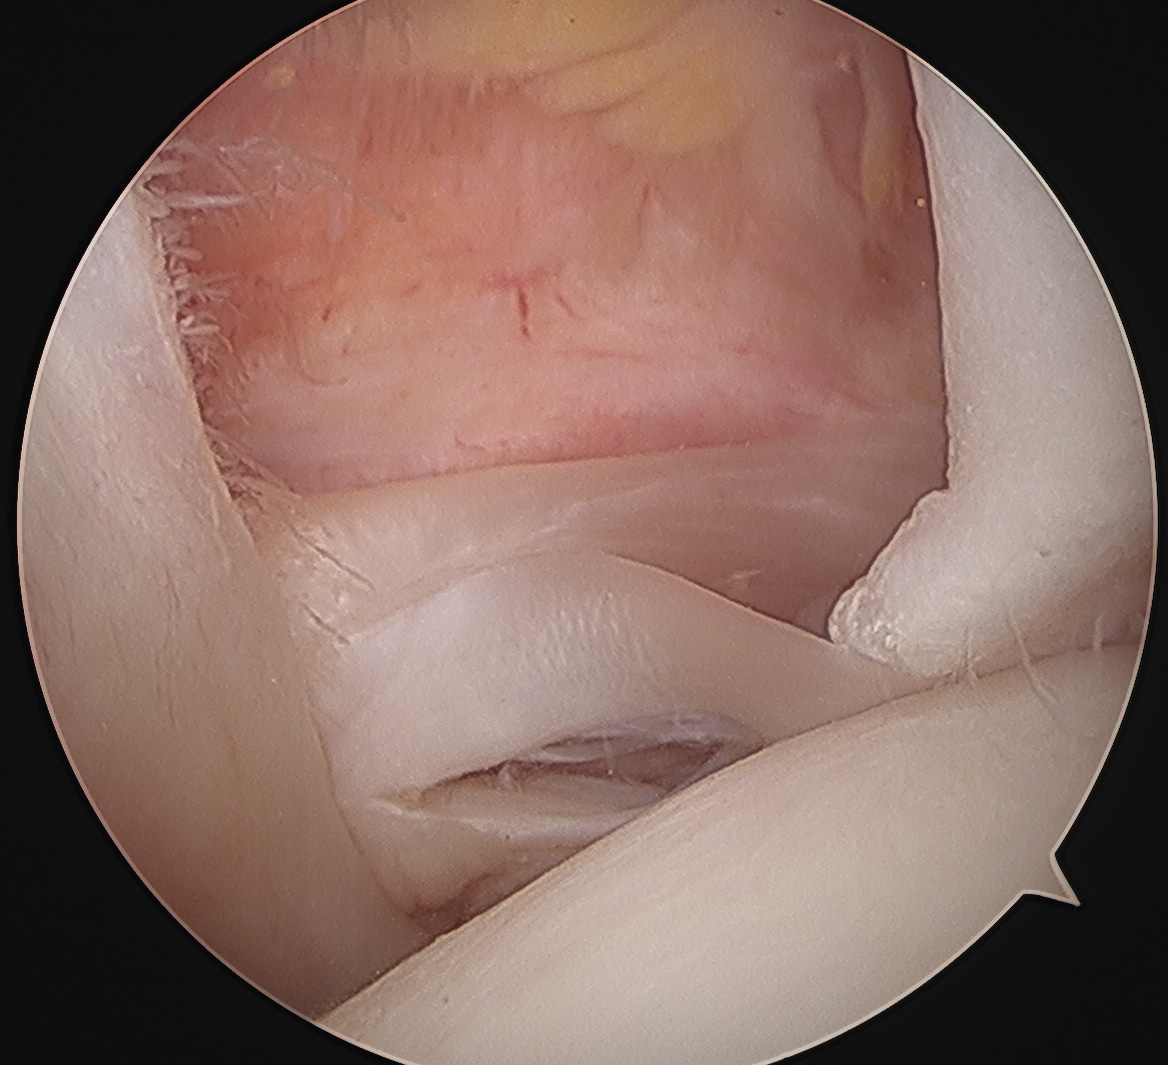

Arthroscopy

Medial subluxation of LHB

Medial subluxation of LBH with subscapularis tear